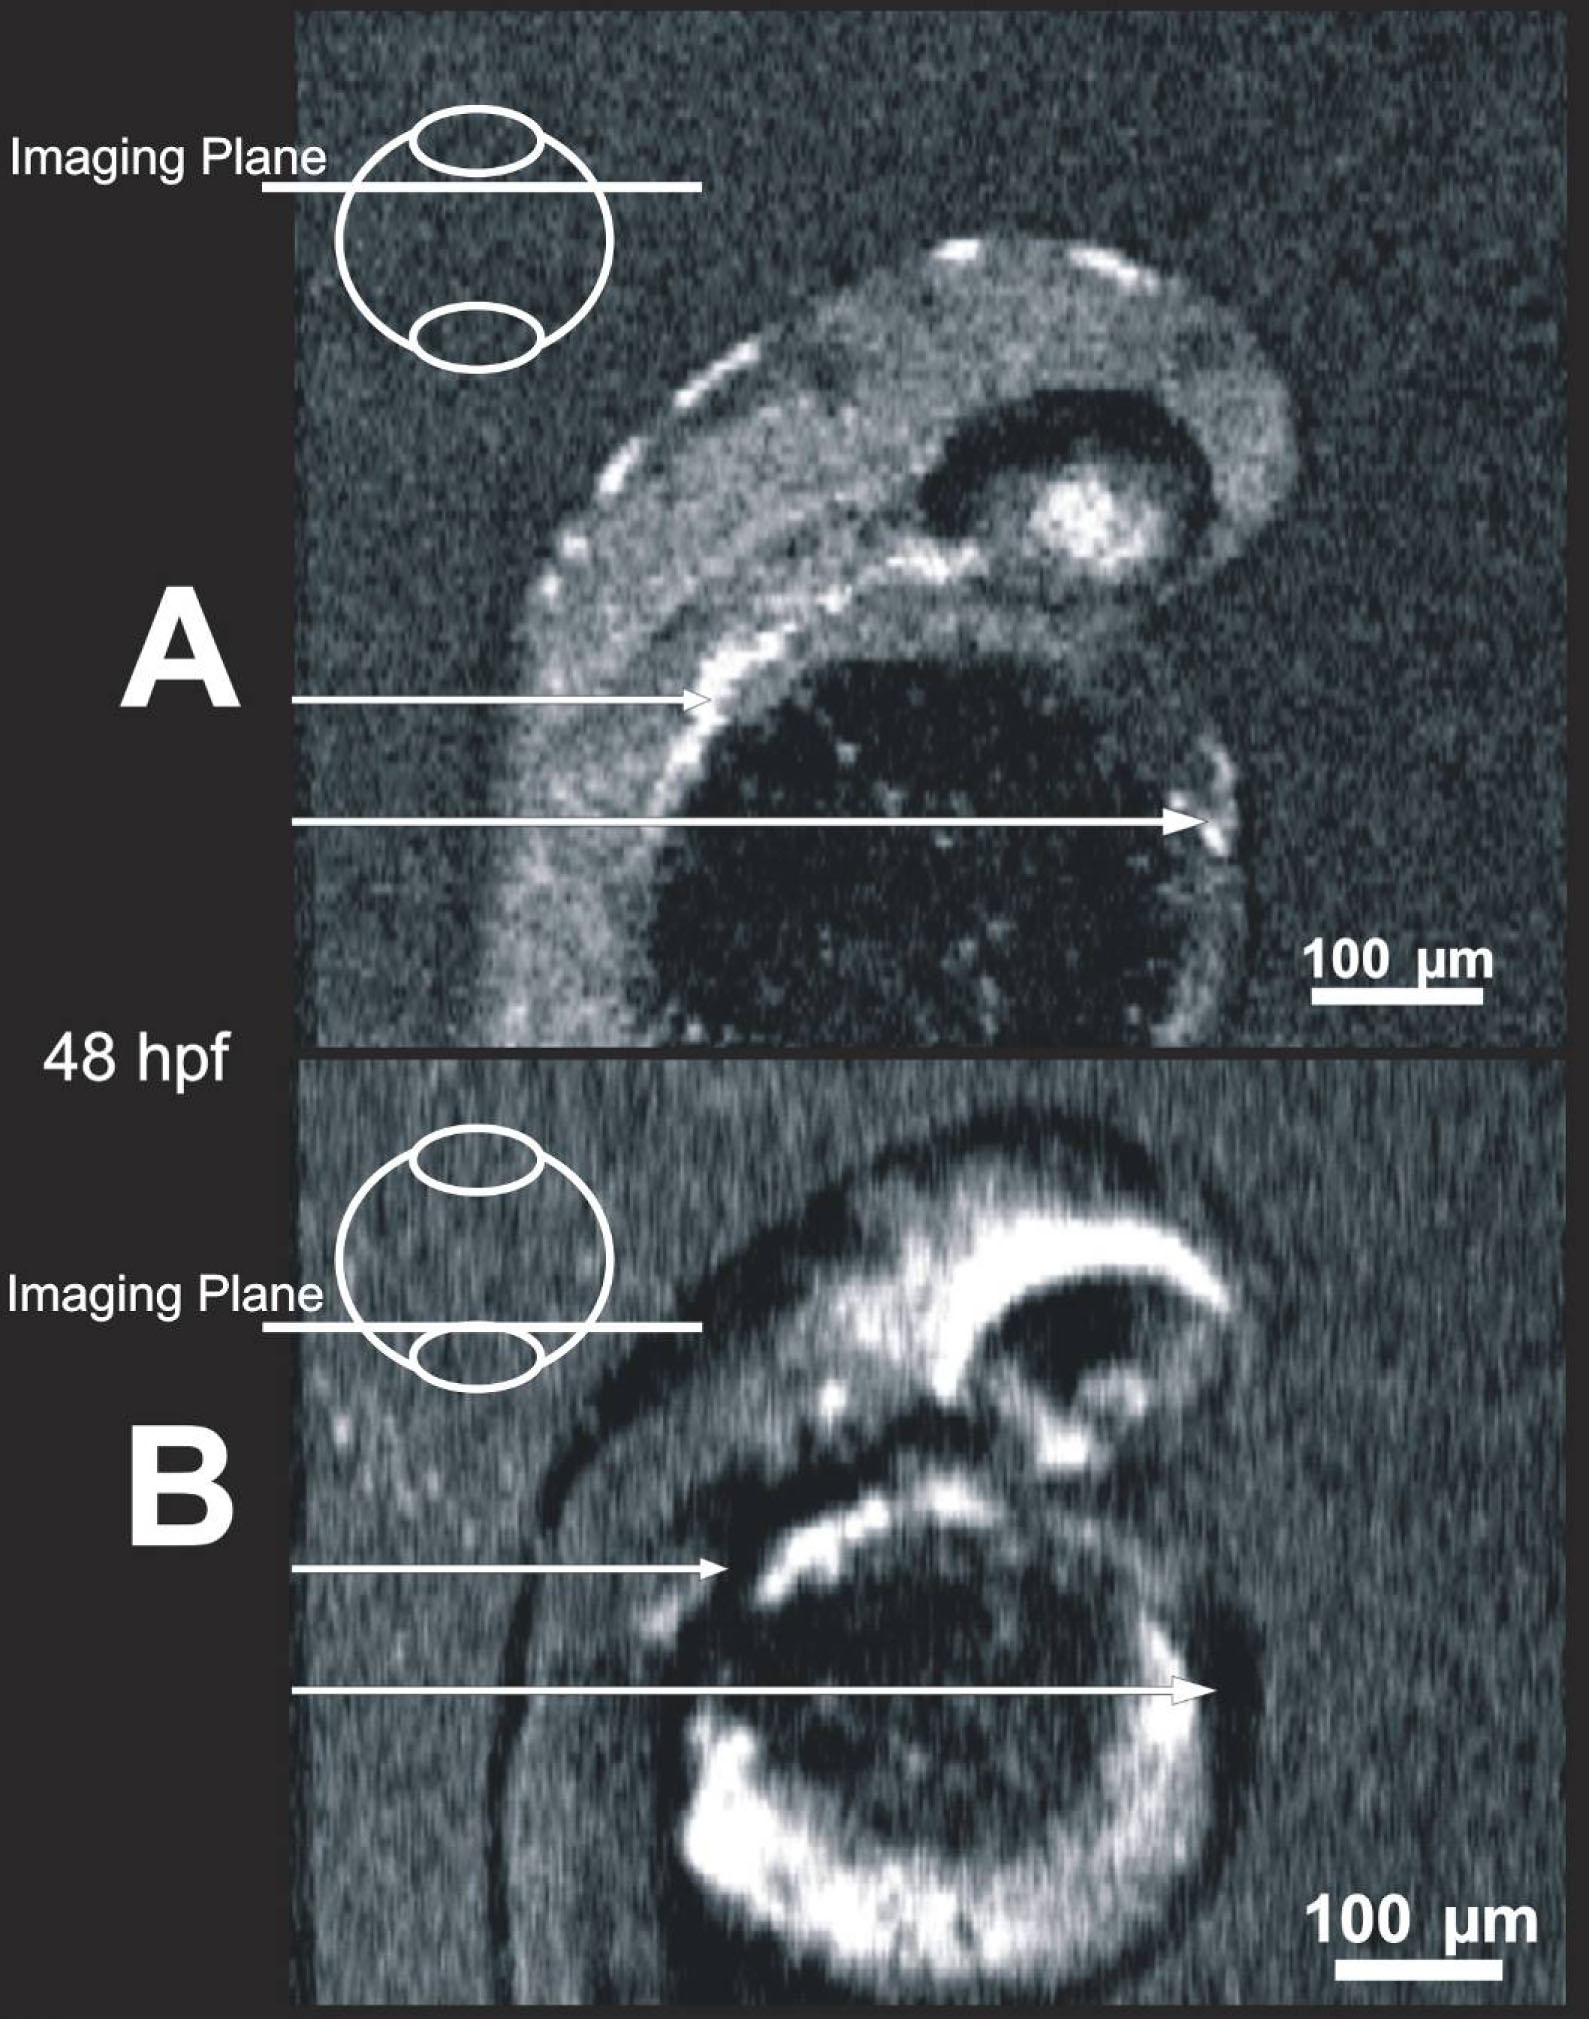

Figure 7. Blood within vessels creates

shadow artifacts in C-mode slices below the vessels. Images of the same

48 hpf embryo obtained in a shallow slab location (A) and a deep

location (B) allow visualization of blood, which is highly

scattering (A, bright locations, arrows), and the resultant

shadows mask structure in deeper slabs (B, dark locations,

arrows).